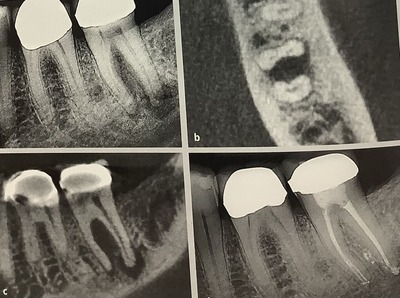

ウ〜ン、お上手です!穴は必要最小限ですが、

しっかりと神経は取り除かれて

先端までピッタリと詰められています。

上手‼︎

曲がった根っこも無理なく、自然なままです。

変に真っ直ぐに削られてません!

辺縁隆線、隣の歯とくっ付いてる肩の所が残ってるので詰め物で十分ですね。

大きく穴をすれば、歯が弱くなりますよね。

根管治療のための穴は小さく出来るんですが、

元々の虫歯があるので出来るだけ歯が残るようにします。

入り口を大きくし過ぎ、上の部分を広くし過ぎると、必要以上に削られて悲しい結果となります。